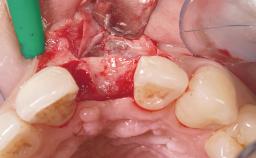

Immediate Flapless Placement of an Implant in a Maxillary Right Lateral Incisor Site

This 43-year-old male patient, a non-smoker, came to our practice because of a fracture of tooth 12 caused by a bicycle accident. Due to the combined para- and infrabony crown and root fracture, tooth extraction, and subsequent implant placement were suggested to the patient as the therapy of choice. The patient had high esthetic expectations with regard to the treatment outcome and asked for an immediate fixed provisional restoration. His individual esthetic risk profile summed up to a medium esthetic risk.

Placement Protocol Immediate implant placement

Tooth Site Maxillary incisor or canine

Socket Morphology Single-root socket

Socket Integrity Sufficient, with intact bone walls